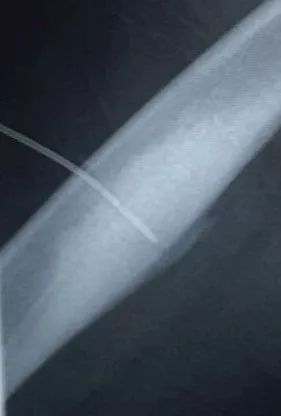

术中,影像引导射频穿刺

术中,劳永锵及潘海文凭借精湛的技术及丰富的手术经验,不断调整穿刺方向,精准直达病灶。在医疗设备科、麻醉科、放射科等各学科的配合,手术顺利完成。